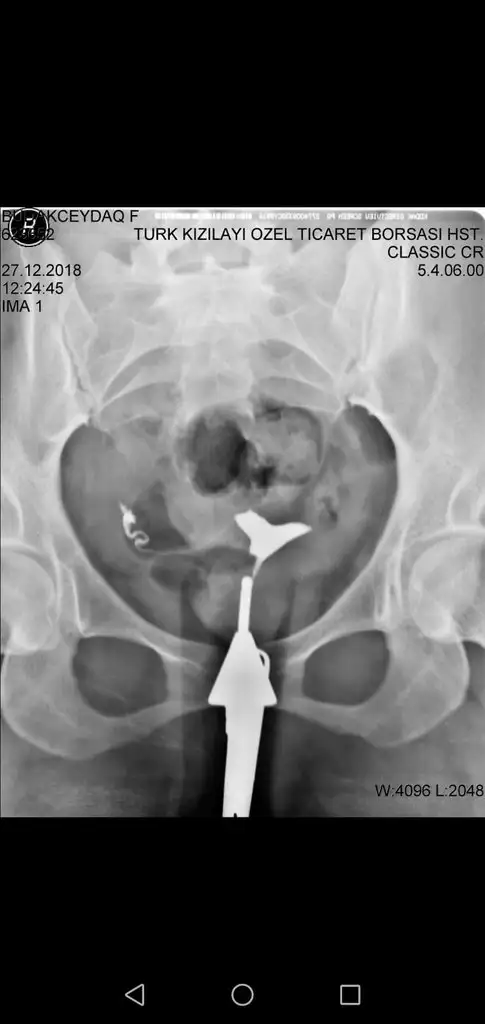

olduğunu düşünmüyorum dedi ay sonu adet başladığında randevu alıp gidicem perde alındı bitti dediler ama sanırsam bana tekrar ameliyat görünüyor benimde rahim filminde Y şekilde foto eklemeye çalışıcam inşallah olur

Eklentiler

• IMG-20190614-WA0004.webp

15,5 KB · Görüntüleme: 356